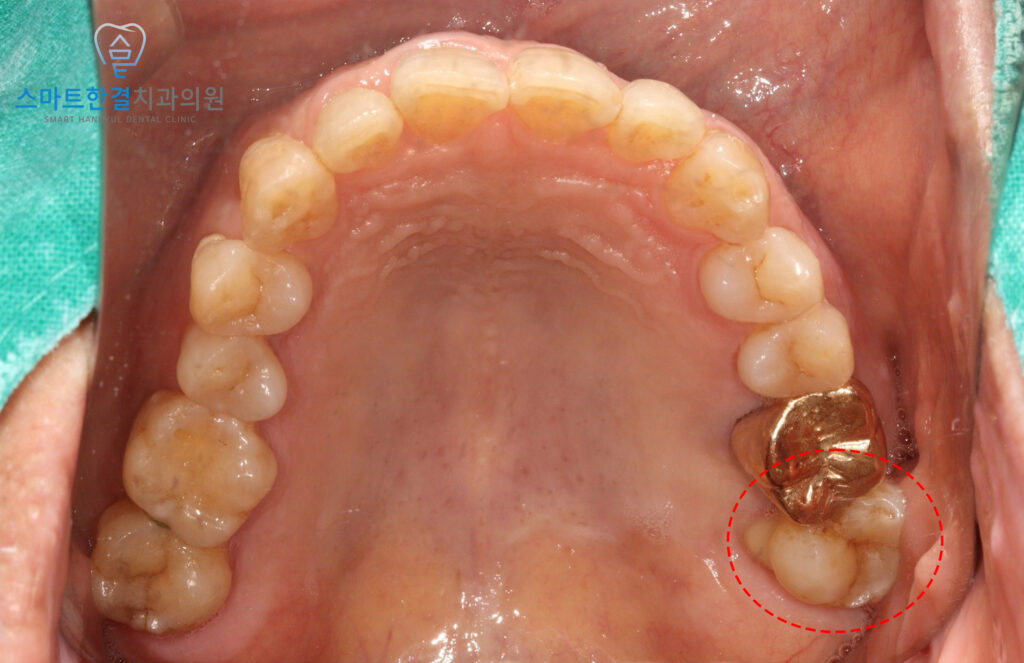

위 환자분께서는 60대 남성분으로,

왼쪽 위 치아의 극심한 통증으로 인해

본원에 내원해 주셨어요.

확인해 보니,

동요도 3도 정도로

심한 흔들림을 보였는데요.

정밀한 확인을 위해

엑스레이 사진을 촬영해 보기로 했어요.

25.09 / 26.01

화서동치과 스마트한결치과의

신경치료 전후 사진이에요.